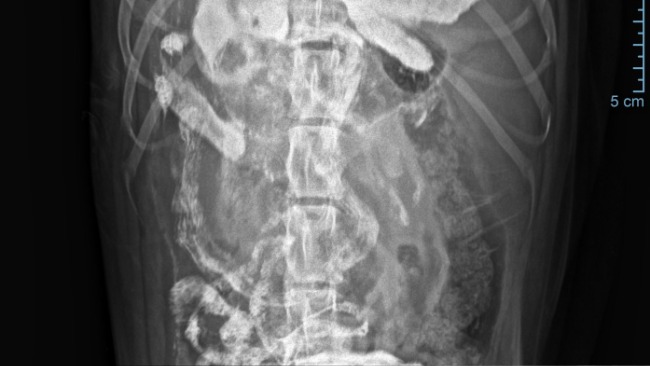

Znowu! Znowu coś się dzieje! Znowu jakaś choroba 😞 Oskarek poczuł się źle końcem grudnia. Jest w trakcie diagnostyki bo niewiadomo co się Mu dzieje a dzieje się uwierzcie mi z psiaka aktywnego, radosnego zrobił się psiakiem apatycznym, sennym nie chcę Mu się nic😞 Boli Go boli go brzuch boli go gęba, chudnie w oczach jest słaby 😭Lekarze obstawiają że to jelita. Dostał antybiotyk i serie zastrzyków, kroplówki.